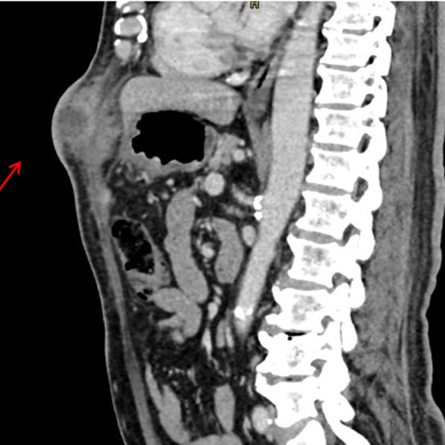

Abdominal actinomycosis by Actinomyces shaaliae georgiae mimicking neoplasia

Case report

Mateo Londoño Barrientos, Carlos Alberto Lopez Zapata, Laura Álvarez Herrera, Marco Frusteri, Carlos Andres Delgado Lopez (Author)

• Páges : e5006672 |

• 92 | 15 | 8 | 2 | 2

DOI: https://doi.org/10.25100/cm.v56i2.6672